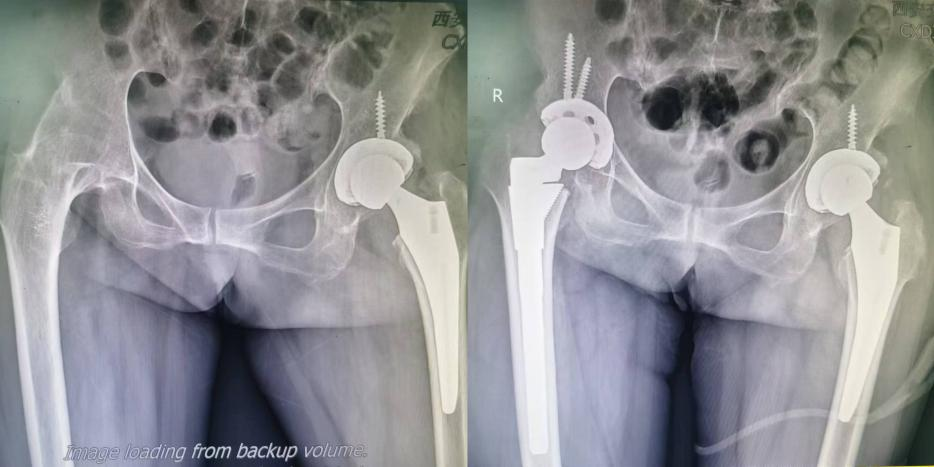

赵女士不幸罹患强制性脊柱炎,导致右侧髋关节完全融合,左侧髋关节继发股骨头坏死,日常生活受到极大影响,曾在国内多家关节外科中心就诊寻求治疗,但均因为全身状况无法耐受麻醉,后辗转慕名到我院关节外科就诊。我院关节外科杨佩主任接诊患者后,积极联系心血管内科、风湿免疫科等科室治疗,并反复邀请麻醉科进行麻醉风险,最终为患者制定了手术方案,分别在今年5月份、8月份在王春生副教授、田润副主任和孔宁医生协助下,进行了机器人辅助双侧髋关节手术。在右侧全髋关节置换术顺利完成的第二天,赵女士扶着拐,高兴的说:从来没想到髋关节可以这么灵活!